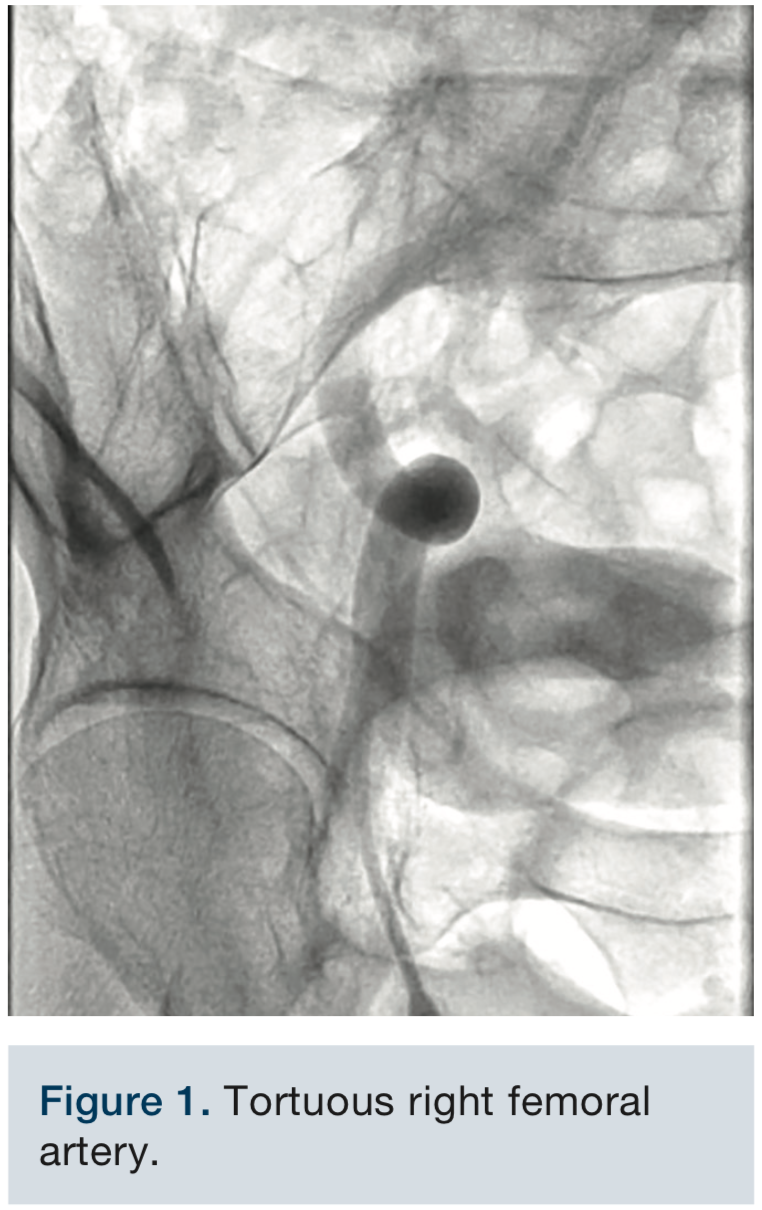

The right femoral artery was accessed at the mid femoral head and a 6 French, 11 cm sheath was inserted. Given a significantly tortuous external iliac artery (Figure 1), a 6 French, 30 cm Flexor sheath (Cook Medical) was exchanged in to aid catheter advancement and manipulation.